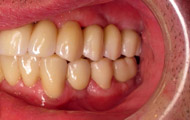

Situation clinique terminée